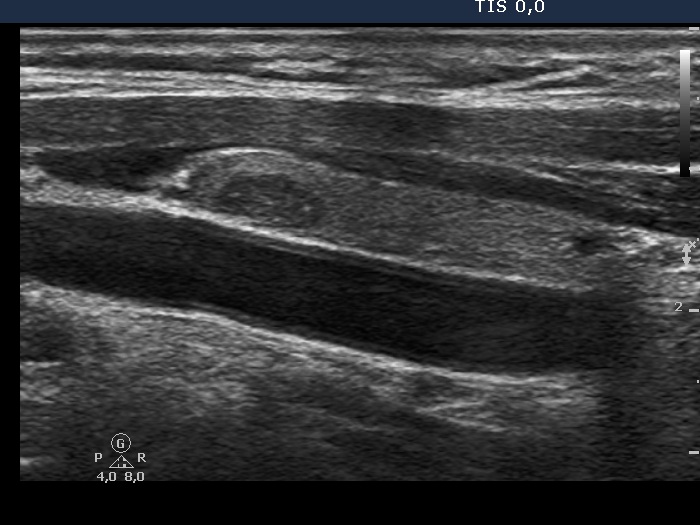

Ultrasonography. The thyroid was echonormal. There was a hypoechogenic nodule with microcalcifications in the right lobe, and another hypoechogenic nodule with microcalcifications and cotton-like patches in the left lobe.

This is a very edifying case as regards the presentation of hyperechogenic figures. Considering the histopathology, these in the right nodule are very likely microcalcifications. On the other hand, they are closer to a non-specific granule.